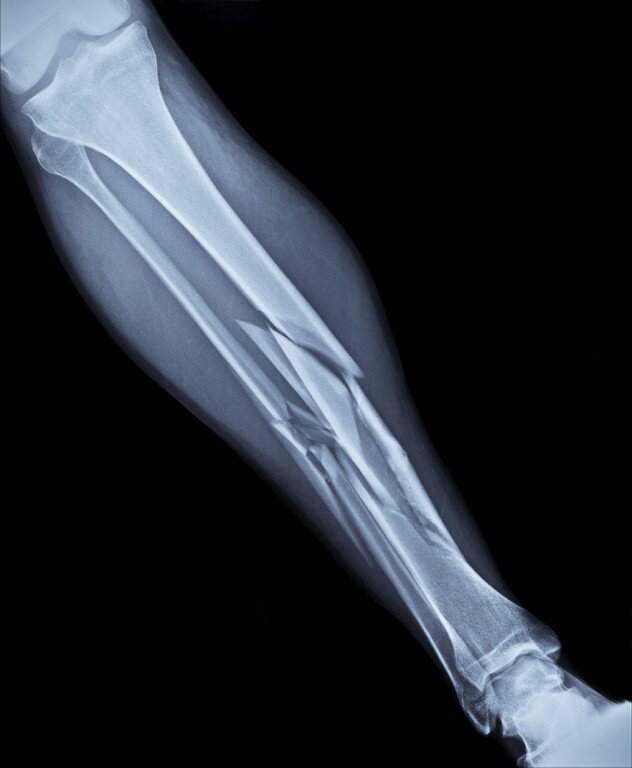

Переломы

- Трещина в кости - это не страшно. На самом деле трещина - это и есть перелом. Просто без смещения и с сохранением перешейка неповреждённой костной ткани.

- Если палец шевелится, значит, он не сломан. Движение не должно стать основным фактором в самодиагностике: чаще всего пострадавшей частью тела можно пошевелить.

- Отёк и боль говорят о переломе. Здесь очень многое зависит от болевого порога человека, который индивидуален: все люди по-разному переносят болевые ощущения. К тому же не обязательно, что боль будет проявляться только в месте травмы - она может распространиться на большой участок, потому что осколки кости повредили соседние ткани.

- Гипс полностью обездвиживает место перелома. Нет, кости продолжают делать минимальное движение даже в гипсе. Поэтому пациентам делают рентген, чтобы в случае чего скорректировать сращивание.

- Сращивание кости - это естественный процесс. Вообще да, но бывают случаи, когда врач отходят от задумки природы и жестко фиксируют кость. Например, ухудшение функции сустава из-за образования костной мозоли.